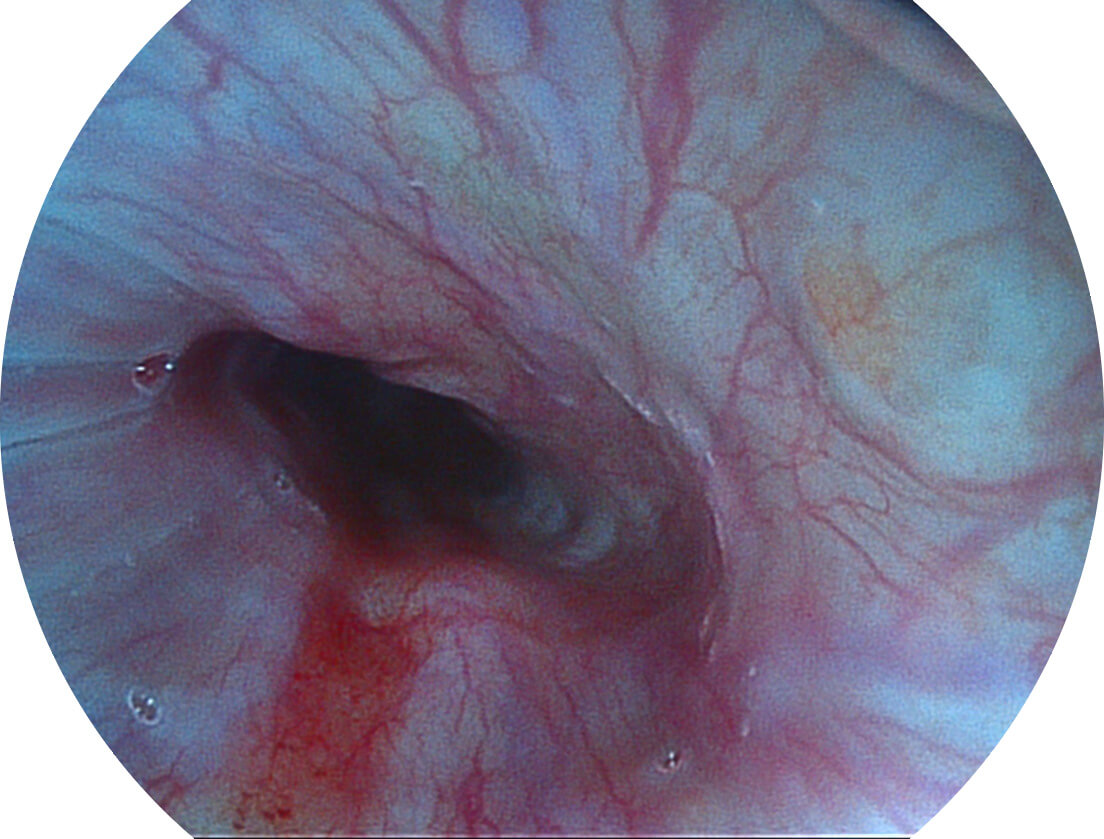

强调浅层黏膜结构的同时,保证照明亮度和提升浅层微血管与中层血管颜色对比度,病变边界更清晰。

VIST图像